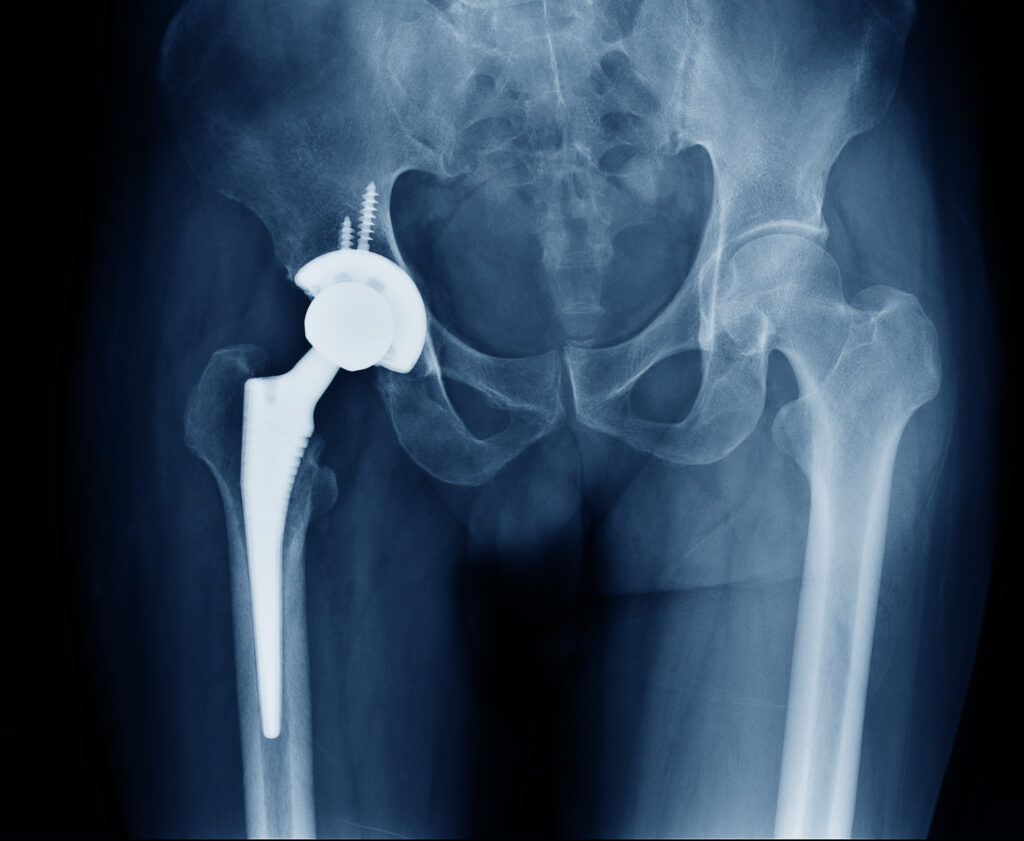

傷んで変形した関節を切除し、人工関節に入れ替えます。

人工関節の材料は金属、セラミック、ポリエチレンが使われており、骨が弱い場合は、骨への固定には骨セメントという樹脂を使用する場合もあります。

術後、大半の方は痛みから解放され、関節の動く範囲も広がり日常生活を送りやすくなります。

近年は材質の進歩が目覚ましく、人工関節のすり減り(摩耗)やゆるみが生じるリスクは非常に少なく、長期の耐久性が期待できます。

THAの術後レントゲン